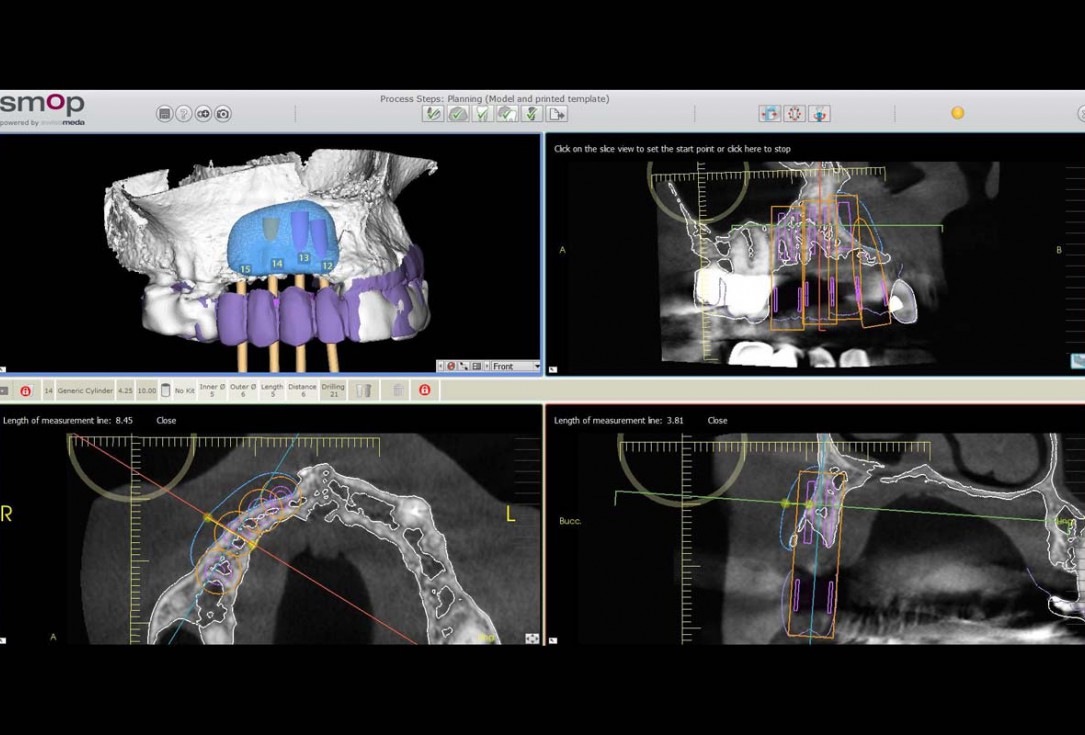

Preoperative situation – Maxillary defect in area 14-16 (loss of implant 16 due to periimplantitis, tooth 14 extracted recently and area 15 already edentulous for a while)